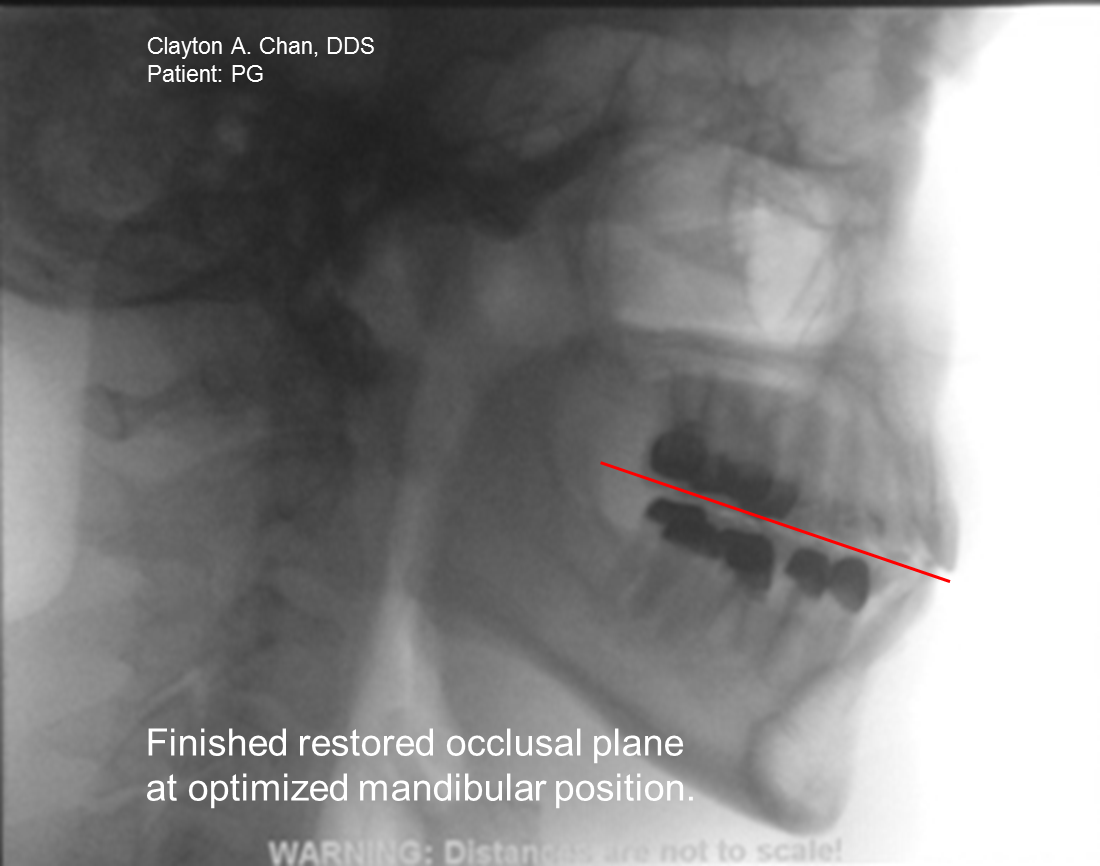

Occlusion Connections Blog What Angle is the Occlusal Plane Relative

Occlusion Connections Blog What Angle is the Occlusal Plane Relative What Is Occlusal Relief An occlusal treatment changes how biting surfaces of the upper and lower teeth. — what is occlusal treatment? — oral splints or mouth guards (occlusal appliances). Often, people with jaw pain will benefit from wearing a soft or. these are occlusal splints that are sold in stores. They are made of a type of plastic that softens. What Is Occlusal Relief.

Occlusion Connections Blog What Angle is the Occlusal Plane Relative What Is Occlusal Relief — occlusal adjustment is selective adjustment of the occlusal surface of teeth by grinding the enamel so that the. these are occlusal splints that are sold in stores. An occlusal treatment changes how biting surfaces of the upper and lower teeth. — stresses and strains of everyday life causing patients to grind or clench their teeth, headaches. What Is Occlusal Relief.